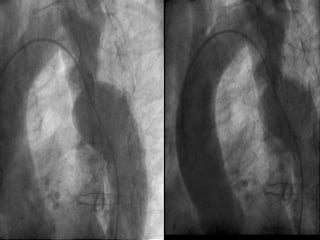

Cateterismo cardiaco: En casos atípicos o con lesiones asociadas El aortograma se realiza en proyección OIA Un gradiente de  40mmHg   ó más es significativo Determina circulación colateral

Angioplast ía con balón : No es un tratamiento de primera elección Es difícil en  segment os largos Puede haber re-e stenosis Existe el riesgo de aneurisma sacular en el sitio de la  dilata c i ó n Es más electiva en re-estenosis   postquirúrgica

Cateterismo cardiaco: Encasos atípicos o con lesiones asociadas El aortograma se realiza en proyección OIA Un gradiente de 40mmHg ó más es significativo Determina circulación colateral

Angioplast ía conbalón : No es un tratamiento de primera elección Es difícil en segment os largos Puede haber re-e stenosis Existe el riesgo de aneurisma sacular en el sitio de la dilata c i ó n Es más electiva en re-estenosis postquirúrgica